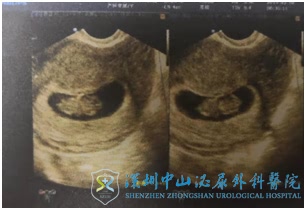

H女士历经3次宫外孕,做了多次试管婴儿,终于在深圳中山妇产医院徐士儒医生的治疗下,成功怀孕,2019年2月份B超发现宫内有一个宝宝,胎心特别有力。

促排过程中,H女士卵巢反应还可以,尤其取卵时内膜形态厚度都很好,徐医生和莫医生商议后决定给她移植新鲜胚胎,这次终于守得云开见月明,等来了期盼已久的好消息:HCG阳性!2月份B超发现宫内有一个宝宝,胎心特别有力,一颗悬着的心可以放下了。医生们也非常期待这个金猪宝宝的诞生,所有的努力和艰辛也终于得到回报。